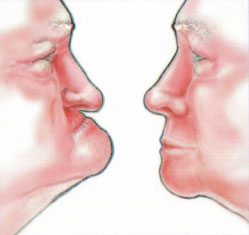

Зубной имплантат - небольшой "искусственный корень", вживляемый взамен утраченного. Имплантат срастается с костью и становится твердой опорой для ваших новых зубов. Если у Вас отсутствует один или несколько зубов, вам не придется обтачивать зубы для установки зубного протеза, если можно установить имплантат, В результате потери зубов на кость уменьшается нагрузка - это приводит к ее атрофии, и смещению зубов в строну дефекта. Со временем появляются морщины вокруг рта, меняется контур лица.

Имплантат будет оказывать нагрузку на кость при жевании, а коронки на имплантате будут поддерживать губы и щеки, помогут вам выглядеть достойно и сохранят форму вашему лицу. Преимушества имплантации 1. Установив имплантат, не придется обтачивать зубы для установки зубного протеза! 2. Имплантат можно установить вместо удаленного зуба в течение одного дня вместе с временной коронкой! 3. Установив имплантат, Ваш съемный протез станет несъемным! 4. Имплантат удержит съемный протез во рту, чтоб протез не выскочил изо рта в самый неподходящий момент. 5. Протезируясь металлокерамическими протезами на имплантате, вкусовые ощущения пищи не изменятся в отличие от съемных протезов которые могут искажать вкус пищи. 6. Установив металлокерамическую коронку на имплантат, улучшается эстетика: уменьшаются морщины вокруг рта, лицо и улыбка молодеет. 7. Установив имплантат улучшается эстетика – коронка на имплантате выглядит так же, как собственный зуб. 8. Установив металлокерамическую коронку на имплантат, Вы восстанавливаете жевательную эффективность на 90%. 9. Уменьшается атрофия альвеолярного гребня кости, восстанавливается нагрузка на кость. 10. После протезирования на имплантате ваше пищеварение будет улучшено, так как пища будет лучше разжевываться и измельчаться, это нормализует работу желудочно-кишечного тракта.